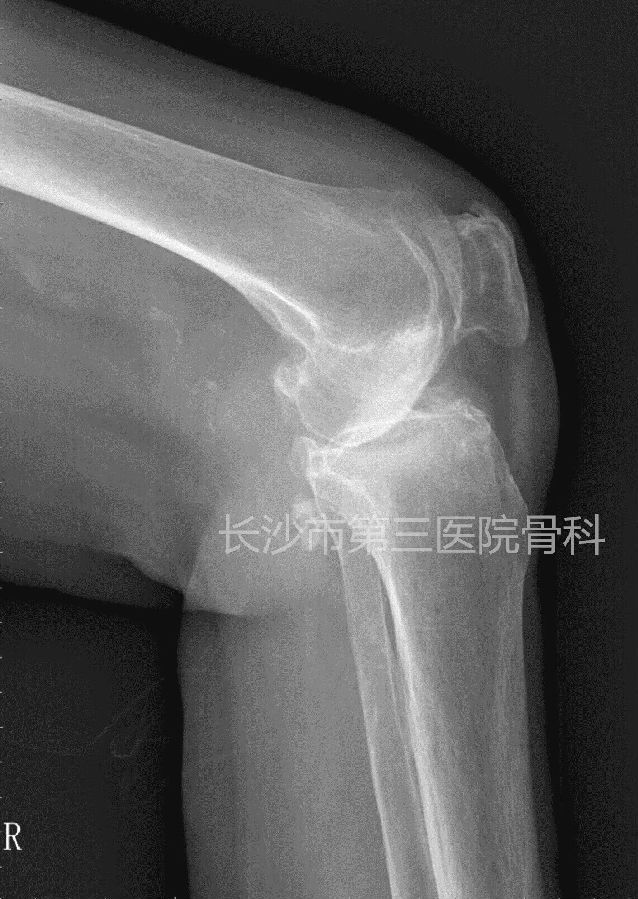

患者李某,女性,76岁。因反复右膝肿痛、活动受限10年,加重4天入院。体查:右膝内翻畸形,屈90度,伸10度,内侧关节间隙及髌骨上缘压痛,侧方应力试验阴性,肌力正常。诊断“右膝骨性关节炎”,为人工全膝关节置换适应症。

术前平片: